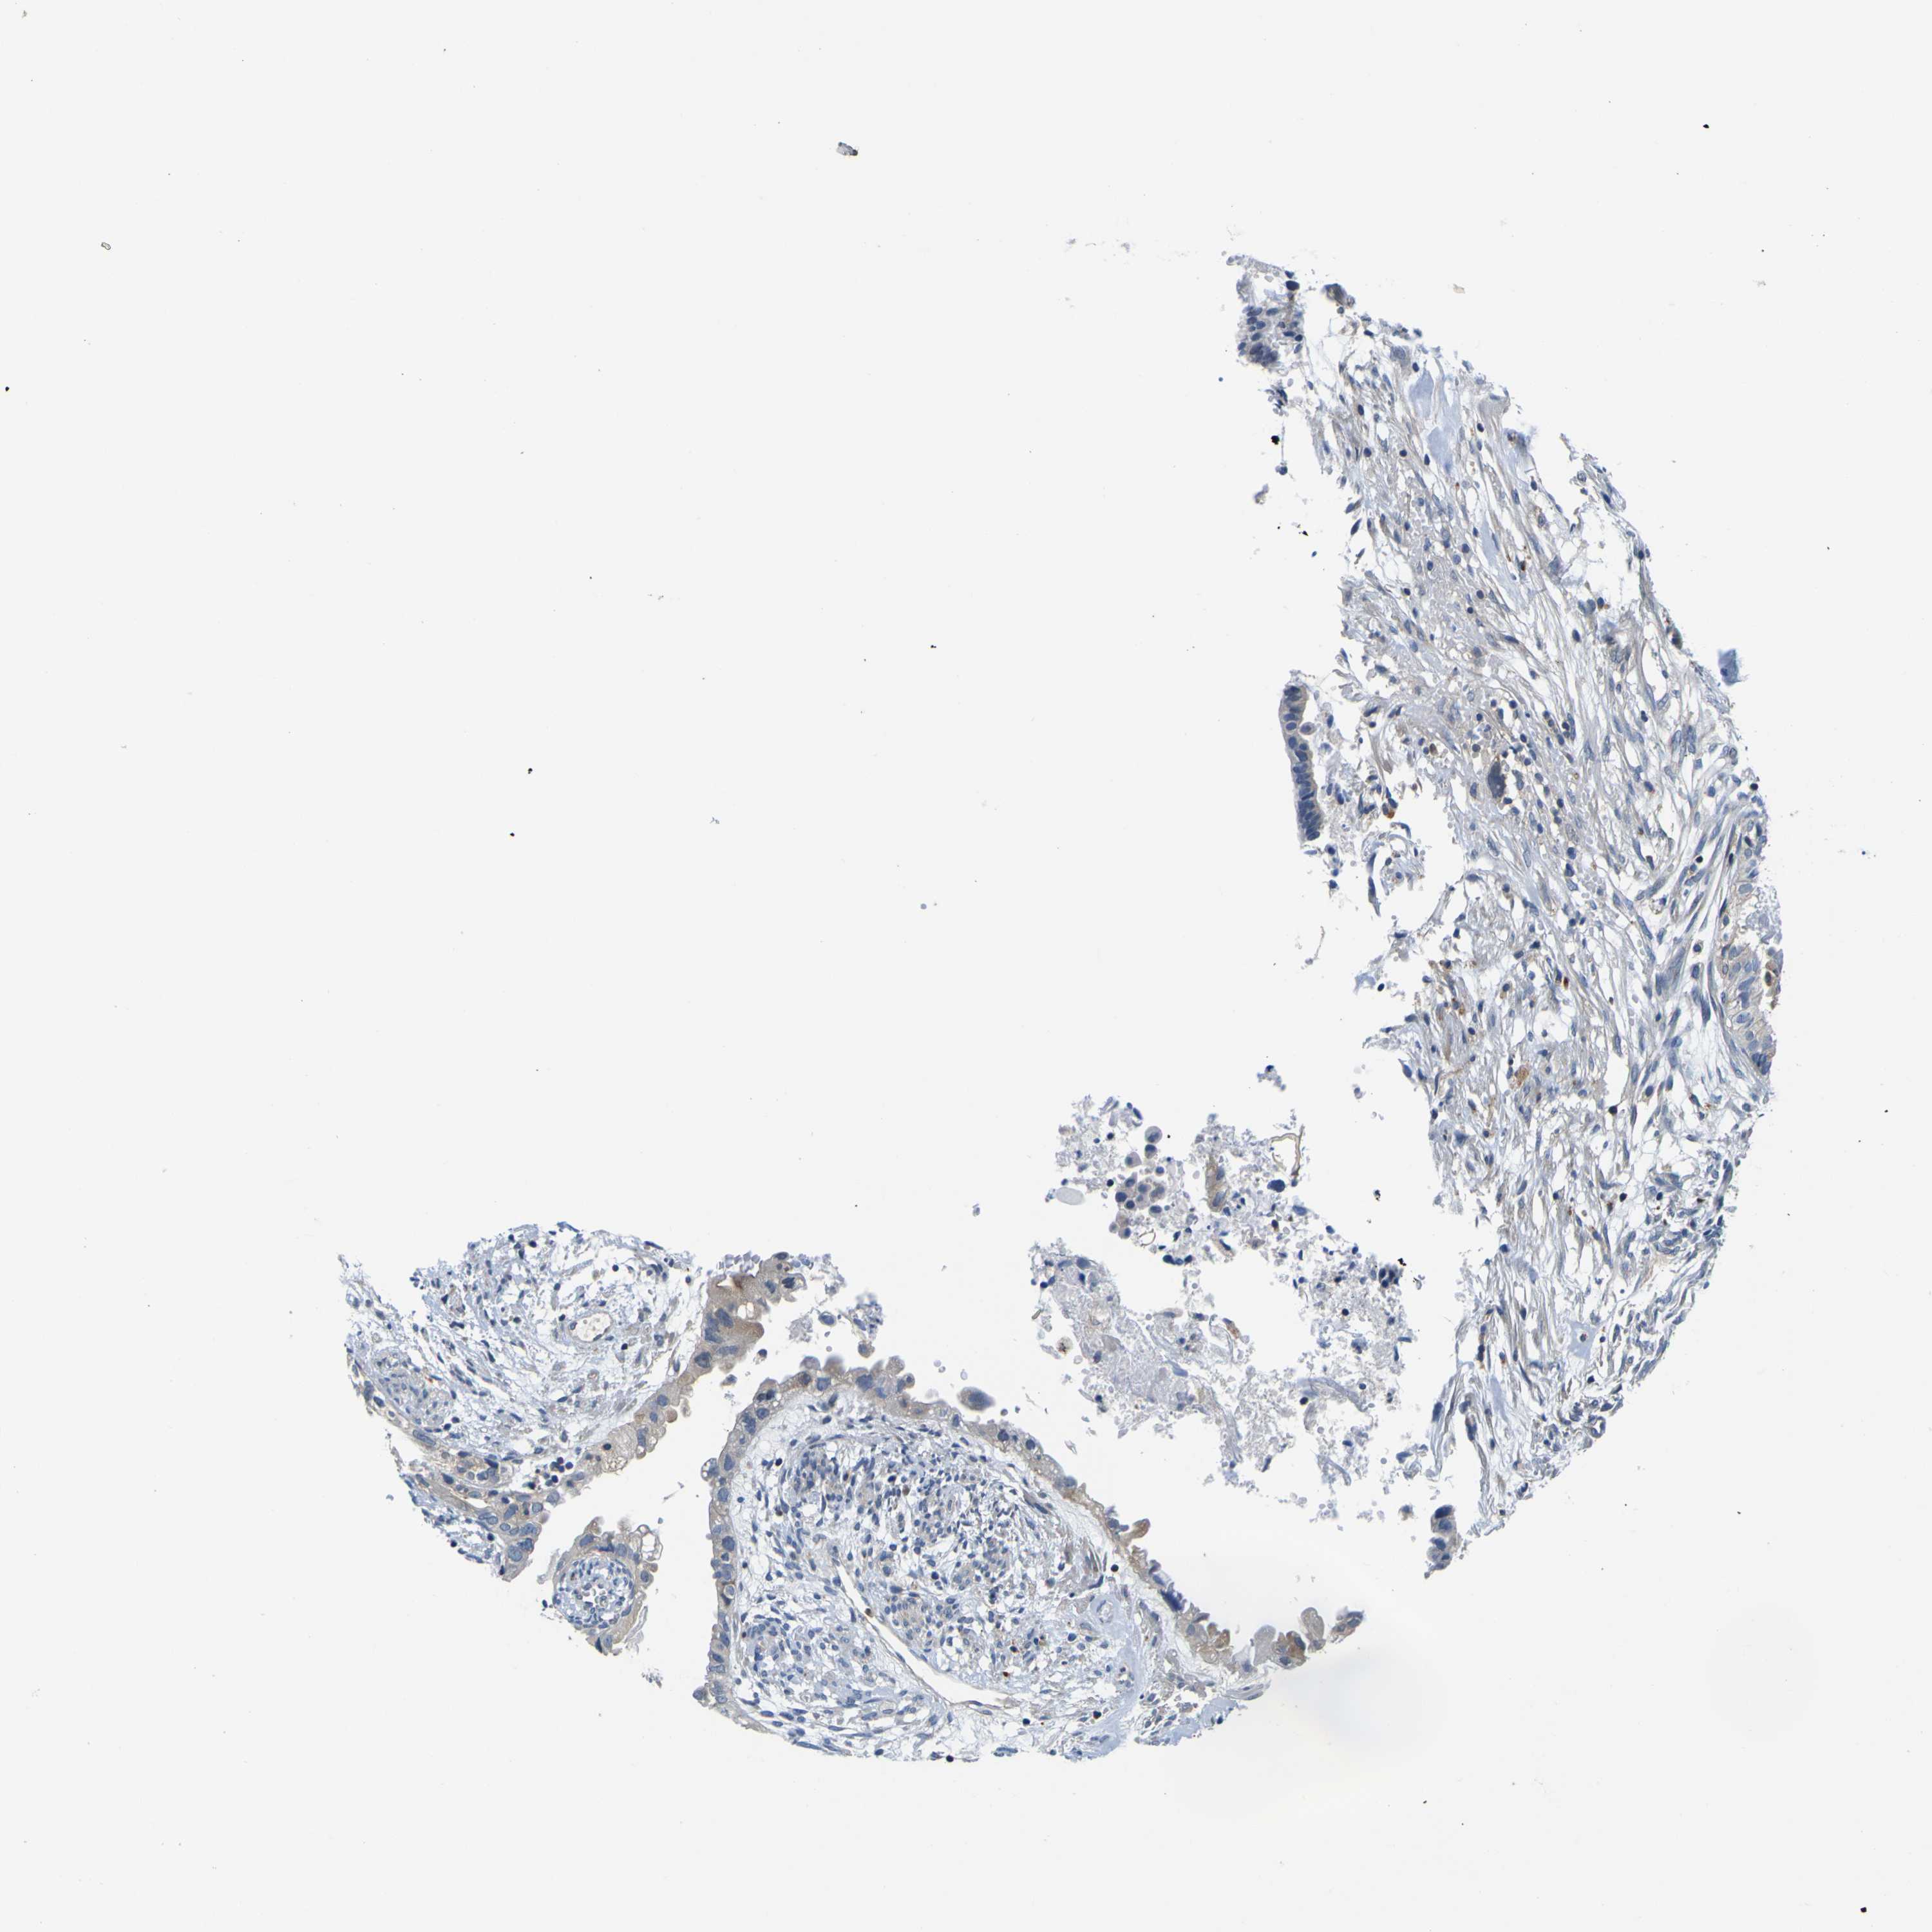

CERVICAL CANCER - Protein expressioni

A mouse-over function shows sample information and annotation data. Click on an image to view it in a full screen mode. Samples can be filtered based on level of antibody staining by selecting one or several of the following categories: high, medium, low and not detected. The assay and annotation is described here.

Note that samples used for immunohistochemistry by the Human Protein Atlas do not correspond to samples in the TCGA dataset.

Antibody stainingi

Antibody staining in the annotated cell types in the current human tissue is reported as not detected, low, medium, or high, based on conventional immunohistochemistry profiling in selected tissues. This score is based on the combination of the staining intensity and fraction of stained cells.

Each image is clickable and will lead to virtual microscopy that enables deeper exploration of all samples and also displays staining intensity scores, fraction scores and subcellular localization as well as patient and tissue information for each sample.

Antibody HPA012128

Antibody HPA012297

Staining

High

Medium

Low

Not detected

Intensity

Strong

Moderate

Weak

Negative

Quantity

>75%

75%-25%

<25%

None

Location

Nuclear

Cytoplasmic/membranous

Cytoplasmic/membranous,nuclear

Squamous cell carcinoma, NOS

Adenocarcinoma, NOS